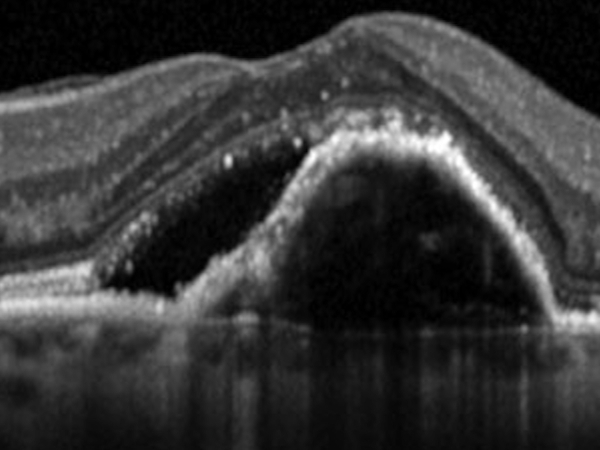

OCT

L’OCT, senza l’utilizzo di mezzi di contrasto, permette, attraverso l’uso di una sonda laser ad infrarossi, di ricostruire l’anatomia della retina nella regione maculare.

Nelle forme di uvette posteriore è dirimente per la diagnosi di edema maculare.